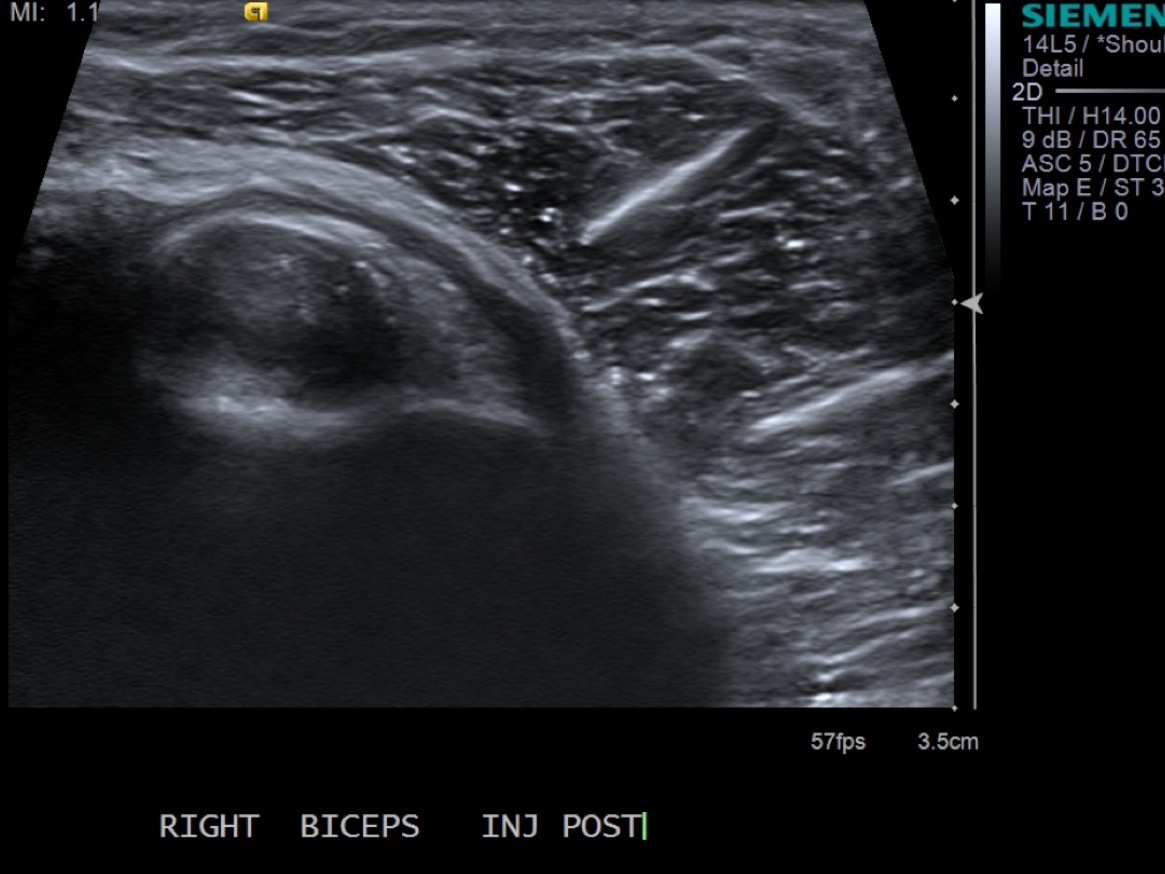

12. Scan sheath to demonstrate distention.

• descriptiondescription